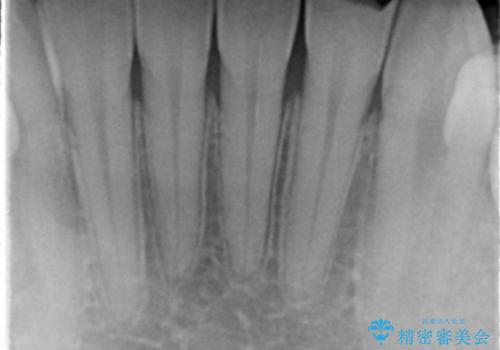

矯正治療前のかみ合わせのせいでかなり削れてしまっていたようです。その場合、矯正治療後に修復するのがおすすめです。

また、クラウンに修復するメリットとして、そのまま使っていると欠けているせいで薄い歯質がうすくなり、さらに割れてしまうリスクを防止することができます。